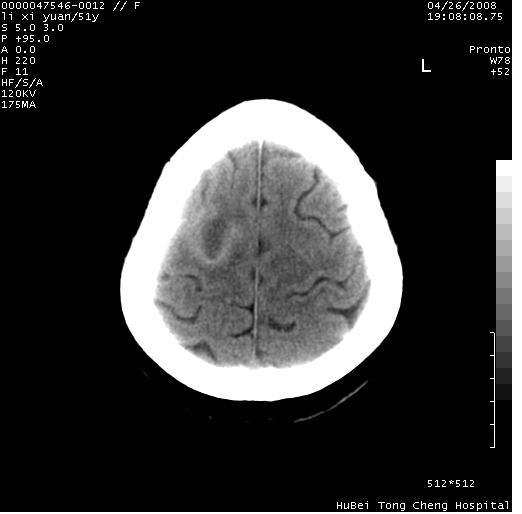

以下是引用余辉在2008-4-27 14:02:00的发言:[br]病灶位于中央沟前方?位于额叶?高密度灶,灶周水肿不明显,病灶似沿脑沟走行,强化明显,局部层面呈现环状强化,考虑1脑表面血管性疾病,如血管瘤,血管扩张,灶内血栓形成,其次考虑肿瘤如脑膜瘤、转移瘤,胶母等

以下是引用形影不离在2008-4-27 14:13:00的发言:[br]考虑胶质瘤可能性大,不排除慢性炎性肉芽肿。建议mri检查。